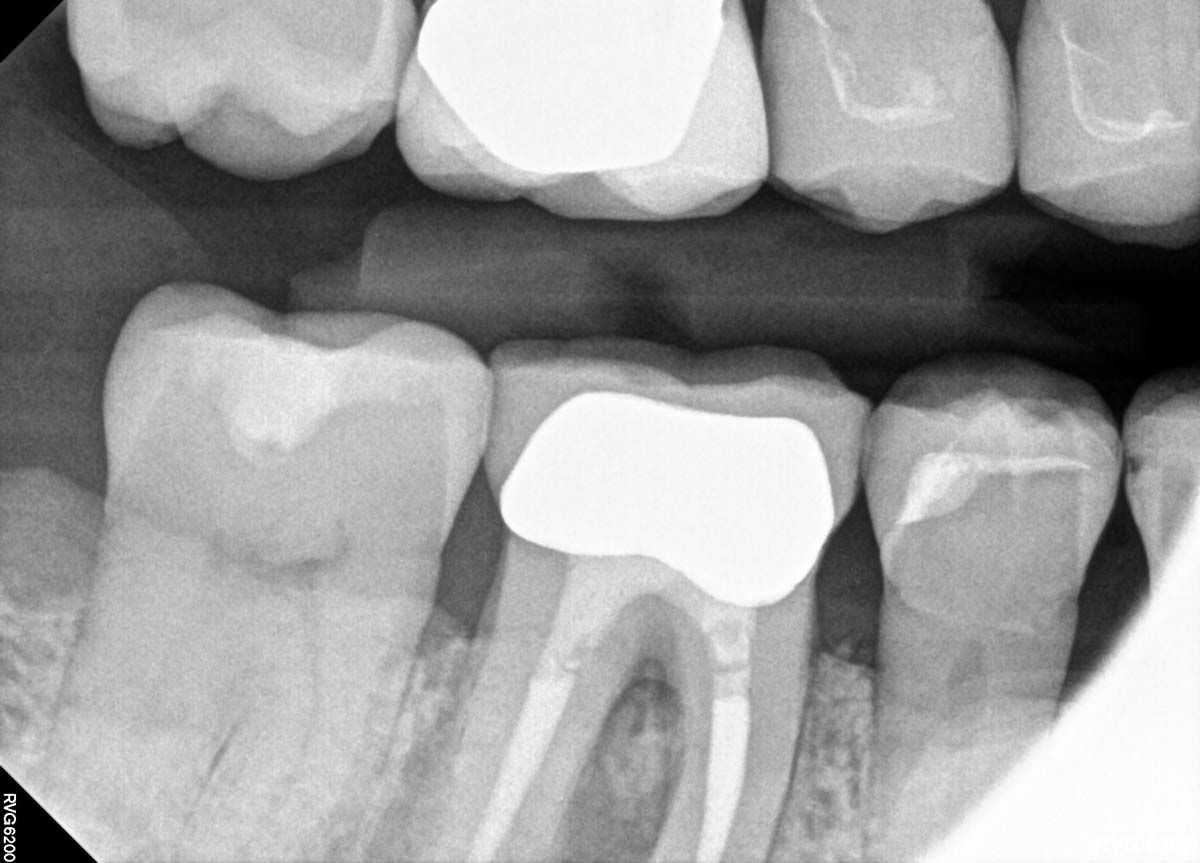

Infection was identified on pariapical x-rays.

A look at patient's periapical x-rays.